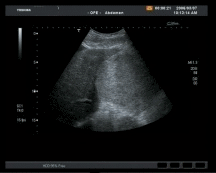

Bei Ultraschalluntersuchungen werden schnell und ungefährlich Informationen über Erkrankungen oder Organveränderungen gewonnen

Abdomensonographie

Grundkurs

Aufbaukurs